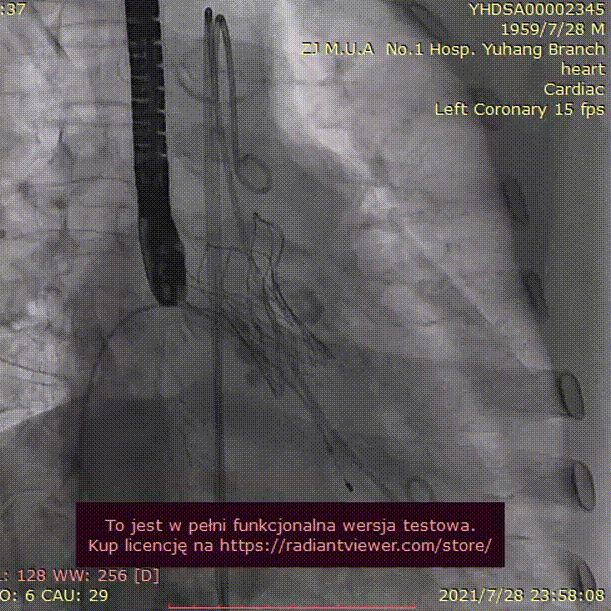

手术过程:

23mm球囊预扩

(有腰征,无瓣周漏,右冠开口阻塞)

TAV24 瓣膜释放前定位

释放4.0*30mm烟囱支架

植入后造影

术后压差1mmHg

术中经食道心超评估: